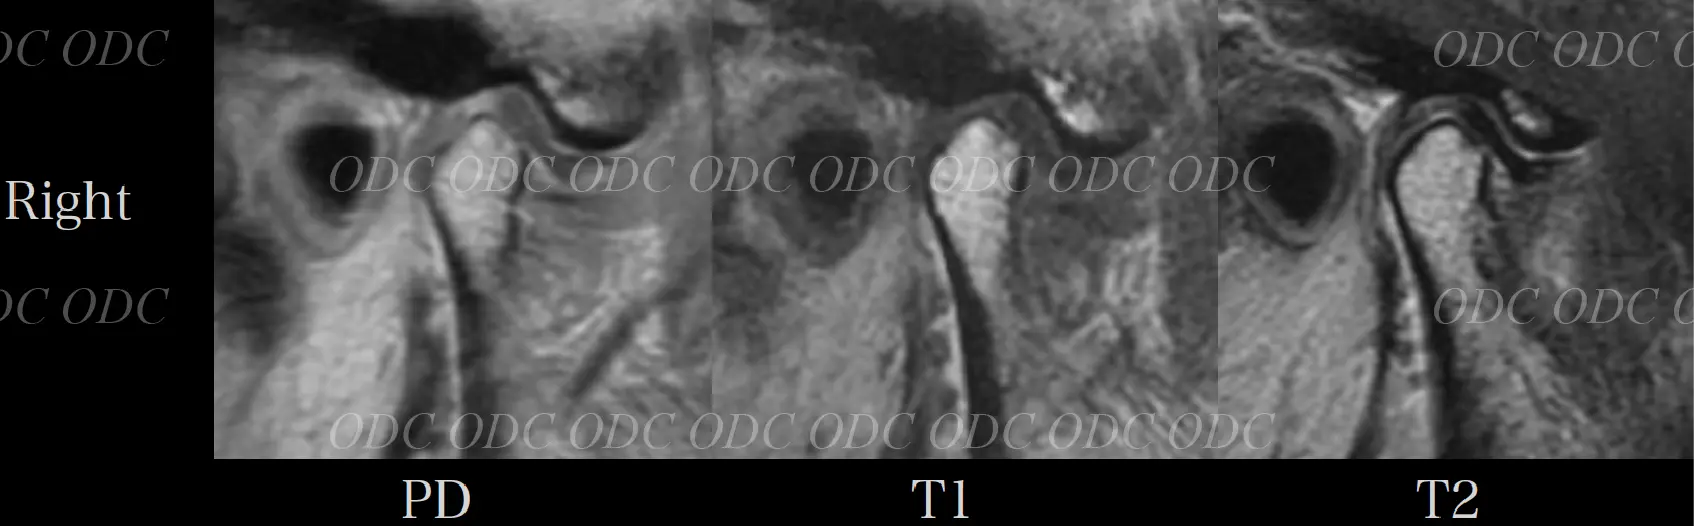

顎関節症 症例

57歳女性。

上顎左側の補綴物の脱離及び全顎的な咬合機能不全を主訴に来院された。

問診をとると、左右顎関節に時々痛みを感じる。

頭痛や肩凝り等の症状も時折みられていた。

多数歯欠損であり、不良補綴物が多く目立つ。過蓋咬合を呈しており、下顎の前方運動に制限があることが推察される。

円板後部結合組織は繊維化を示し、偽円板化を示している。右側で顕著である。

両側下顎頭に骨髄信号の異常は認められない。両側関節円板は前方転位をしている。

初診時に患者が訴えていた顎関節部の痛みはこれによるものと思われる。

両側上下関節腔に貯留が認められ、特に右側で顕著である。

両側関節円板は前方転位をしている。後部結合組織は両側共にさらに偽円板化が亢進したことが分かる。両側上下関節腔に認められていた液貯留がほぼ消失した。

定期的にMRIを撮影し、顎関節の状態を把握しながら治療を進めてきたので、咬合再構成による顎関節への大きなダメージを与えることなく治療を完了することが出来たと考察した。